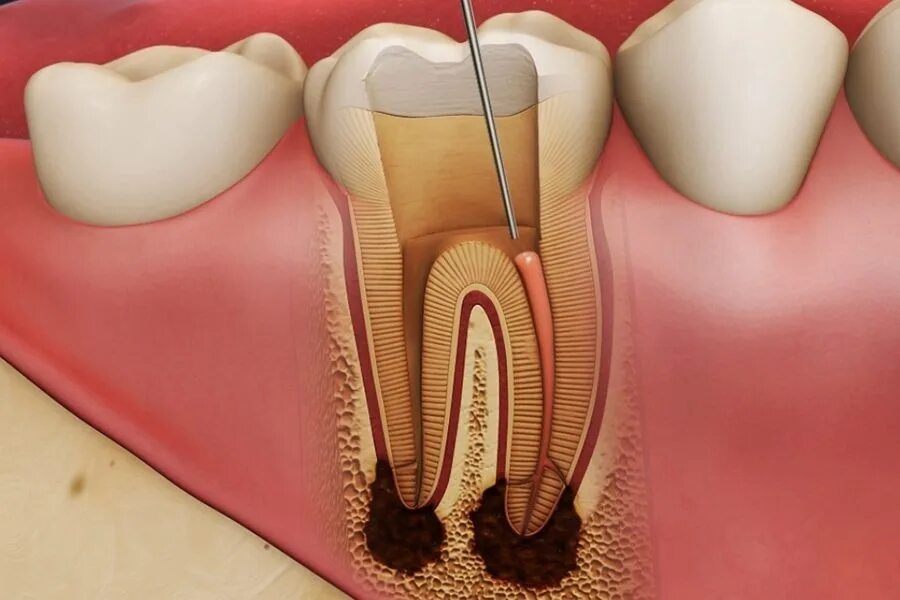

Зуб с удаленным нервом